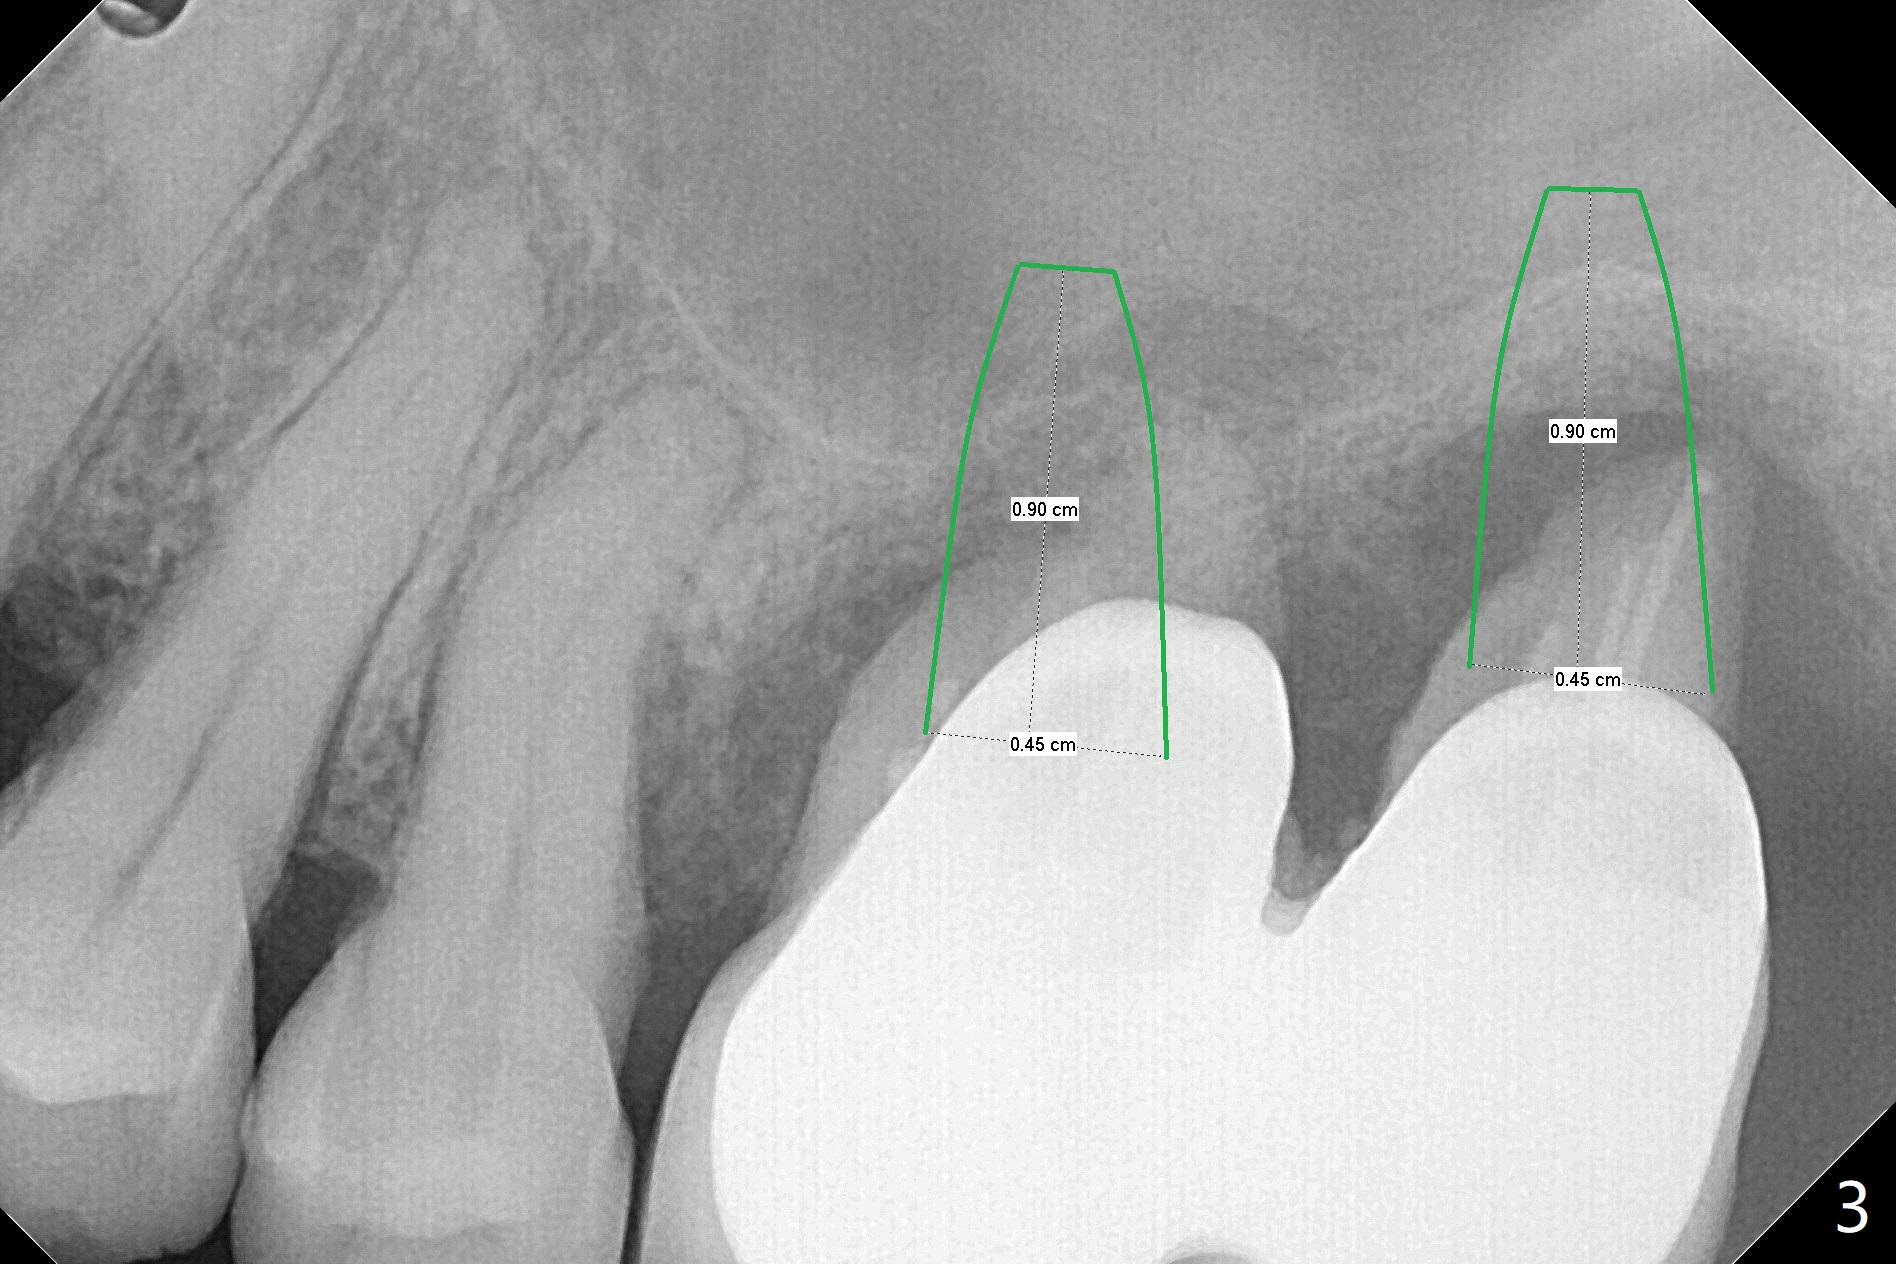

54岁女左上6,7连冠松动,牙槽窝大而敞开,似乎只有即刻植牙即刻修复能够固定粘性骨粉(抽血x2,图三),残余骨壁很薄(2-3 mm,图二),上颌窦内提升应该容易,使用Magic Sinus Lift Kit,其实6腭侧根可能已经进入上颌窦(图一:*)。两张PRF膜当中剪个洞,放置植体开口,然后插入基台,膜周围与牙槽窝开口接触,牙龈下1-2毫米,在膜下面再放置适当骨粉,膜表面放置湿纱布(防止树脂与膜粘合),然后制作临时牙冠。